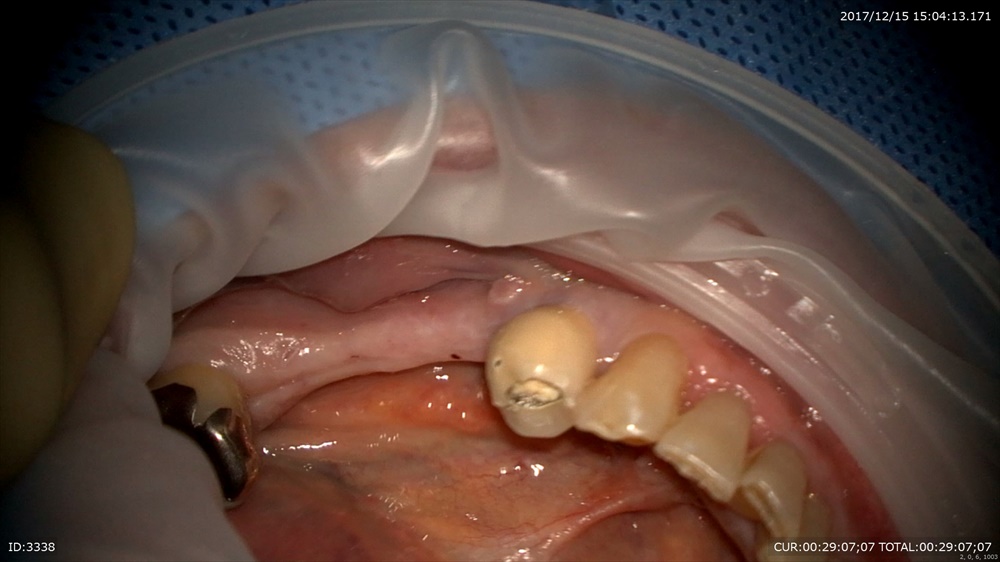

ラバーダムをして

丁寧に 巨大なむし歯

診断の通り神経がみえました。